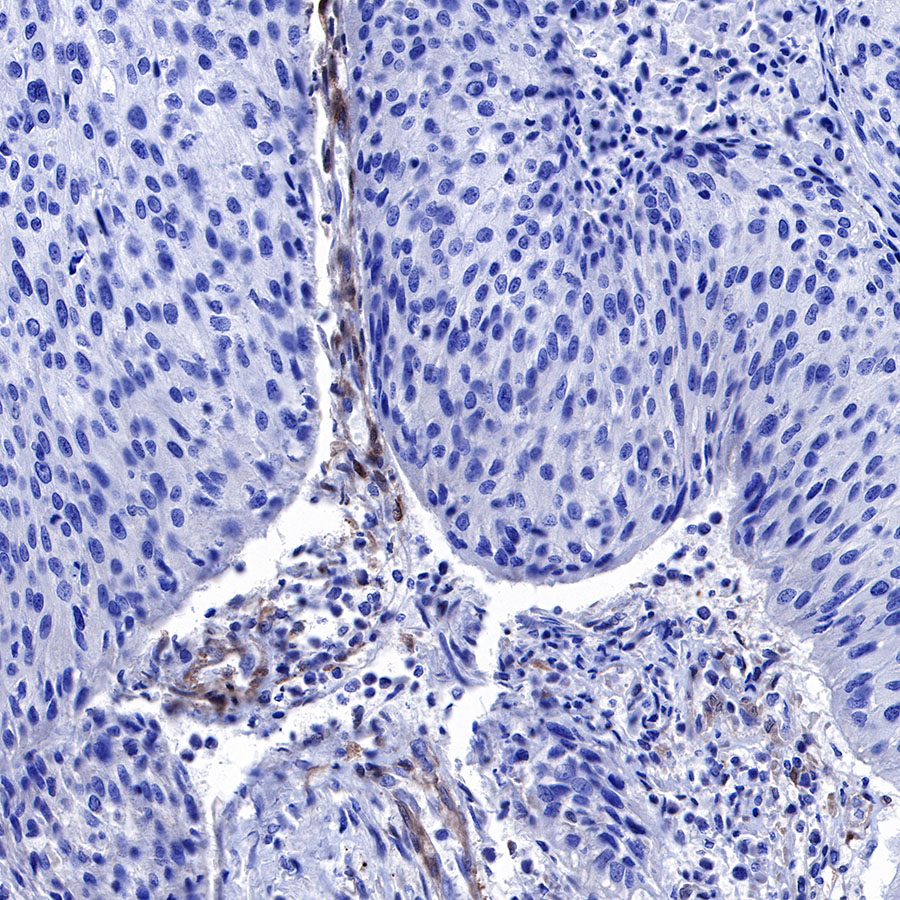

Immunohistochemistry

IHC shows positive staining in paraffin-embedded human cervical carcinoma. Anti-PTEN antibody was used at 1/500 dilution, followed by a HRP Polymer for Mouse & Rabbit IgG (ready to use). Counterstained with hematoxylin. Heat mediated antigen retrieval with Tris/EDTA buffer pH9.0 was performed before commencing with IHC staining protocol.